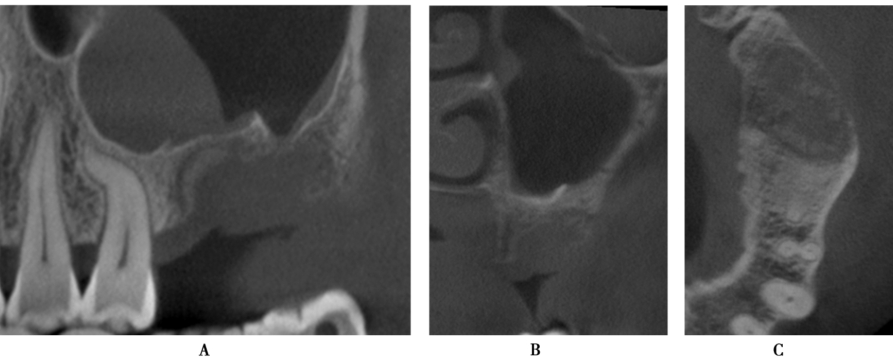

术前CBCT显示缺牙区牙槽嵴顶到上颌窦底的最小高度约3mm,上颌窦底黏膜约1mm,上颌窦腔影像清澈,无炎症,侧壁厚度1~2mm(图12)。

图12 术前CBCTA.冠状面;B.矢状面

超声骨刀侧壁开窗,剥离上颌窦黏膜(图13A)。但在剥离的过程中,由于开窗中央骨块锐利的边缘,侧壁上颌窦黏膜发生穿孔(图13B)。采用胶原膜封闭穿孔后,植入Bioss®骨粉,采用延期种植。

图13 侧壁开窗A.超声骨刀开窗;B.分离窦黏膜,但出现小的穿孔

术后CBCT,见上颌窦内有血液充盈,但骨粉充填良好,未见骨粉弥散,保持了良好的形态(图14),提示胶原膜对穿孔起到了良好的封闭。

图14 术后CBCT,可见窦腔有积液A.矢状面;B.冠状面